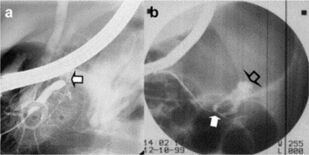

В монографии изложены современные рекомендации по диагностике и лечению сочетанной закрытой травмы живота, основанные на отечественных и зарубежных публикациях из электронных баз медицинской литературы PubMed, Cochrane Library, Scopus, Embase, ScienceDirect, Google Scholar Search, eLibrary, анализе многоцентровых исследований, систематических обзоров, метаанализов, больших серий случаев, оригинальных статей и рандомизированных контролируемых исследований с указанием уровней доказательств и силы рекомендаций.

Предложен оригинальный алгоритм диагностики и лечебной тактики при сочетанной закрытой травме живота, позволяющий стандартизировать ведение данных пациентов, дана детализация данного алгоритма при повреждении конкретных органов и систем, описана концепция damage control, уточнены показания к методам диагностики, консервативному лечению, видам оперативных, эндоваскулярных и малоинвазивных вмешательств в зависимости от степени тяжести травмы органов.